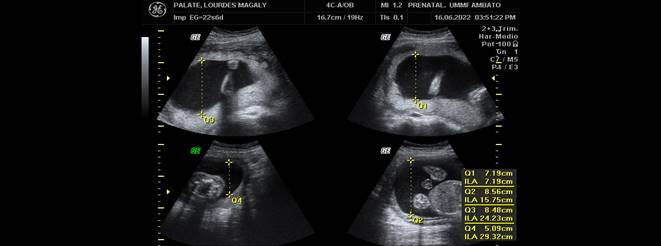

Llama la atención altura de fondo uterino discordante con la fecha de ultima menstruación que en este caso si es confiable, motivo por el que solicito ecografía obstétrica de control a las 22 semanas de gestación en donde se evidencio (Figuras 1,2 y 3).

Figura 1. Ecografía obstétrica del segundo trimestre de gestación con un embarazo de 22s que indica el índice de líquido amniótico en 29,32cm (4 bolsillos)